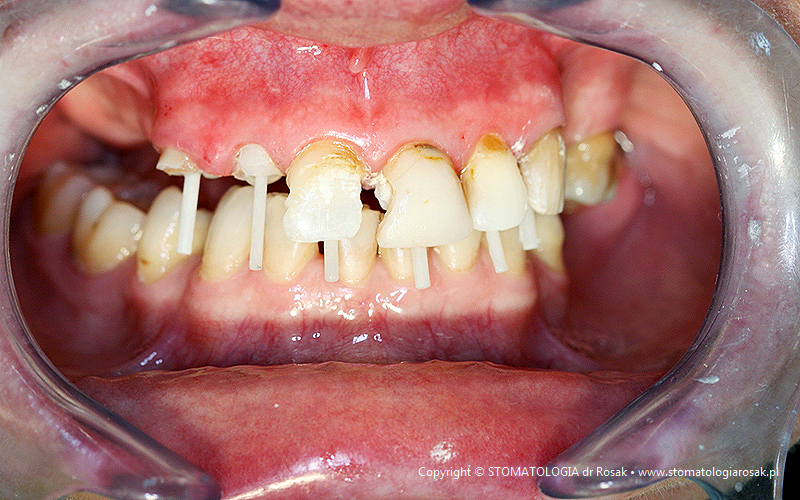

6. Pacjentka lat 56 z zaawansowaną próchnicą zębów i rozległymi brakami zębowymi zgłosiła się celem usunięcia zniszczonych zębów i wykonania ruchomej protezy – wykonano kompleksowe leczenie zachowawcze i mosty porcelanowe z zastosowaniem systemu podparć szklanych ZX-27…dzięki temu wyeliminowano ruchomą protezę i zyskano komfortową pracę stałą.

| 6a. Sytuacja wyjściowa |

6b. Stan uzębienia po oczyszczeniu próchnicy |

| 6c. Wzmocnienie kanałów korzeniowych po leczeniu endodontycznym wkładami z włókien szklanych |

6d. Odbudowa rdzeni koronowych |

| 6e. Most porcelanowy wykonany z zastosowaniem nowoczesnego artykulatora |

6f. Gotowy most porcelanowy z podparciami szklanymi ZX-27 |

| 6g. Gotowy most porcelanowy |

6h. Pod ostatnim zębem widoczne podparcie szklane ZX-27 |